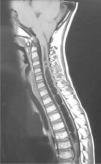

Se realizó una gammagrafía ósea de pelvis y MMII (fig. 1) sin alteraciones en caderas, mostrando menor captación derecha. Ante la sospecha de un proceso con afectación crónica del lado derecho, se realizó resonancia magnética cerebral y medular (figs. 2 y 3) y se diagnosticó de malformación de Arnold-Chiari tipo 1 (MCI) y siringomielia extendida hasta T8. El paciente fue derivado para intervención neuroquirúrgica que resultó exitosa.